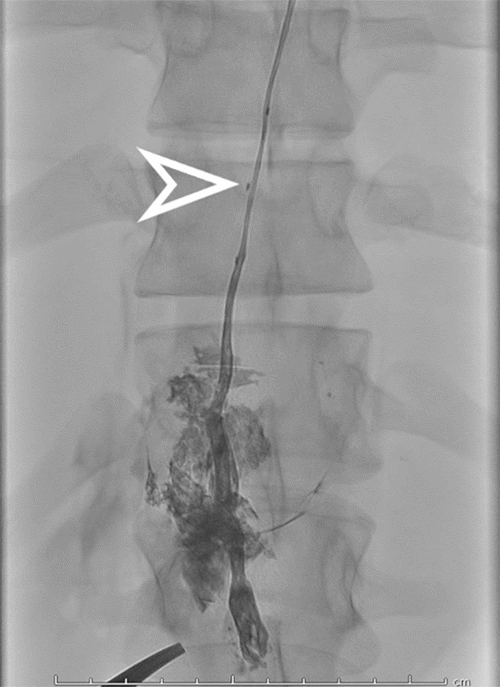

Interventional radiology performed a lymphangiogram to evaluate lymphatic drainage of the pelvic, abdominal, and thoracic regions. The study identified active extravasation from the thoracic duct near the clavicular head. The interventional radiologist then embolized the leaking segment using coils and glue (Figures 3-6). While chest tube drainage briefly declined, it returned to pre-procedure levels by postoperative day 2.

Figure 5. Lymphangiogram: Active Contrast Extravasation (arrow). Published with Permission

Repeat chest CTA revealed a localized air-fluid collection in the left hemithorax, concerning for empyema. However, imaging review suggested an anatomic variant: a posteromedially positioned thoracic duct coursing along the left aorta, lateral to the vertebral column. Given this anomaly, a second IR embolization attempt was undertaken. Accessing the thoracic duct via the left neck proved challenging due to its proximity to the subclavian junction. Therefore, we opted for a re-approach of the previously embolized cisterna chyli through the epigastrium, followed by successful repeat embolization with glue (Figures 7-10).